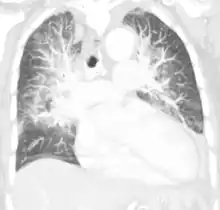

![]() | |

| Pulmonary edema with small pleural effusions on both sides | |

Low oxygen saturation in blood and disturbed arterial blood gas readings support the proposed diagnosis by suggesting a pulmonary shunt. A chest X-ray will show fluid in the alveolar walls, Kerley B lines, increased vascular shadowing in a classical batwing peri-hilum pattern, upper lobe diversion (biased blood flow to the superior parts instead of inferior parts of the lung), and possibly pleural effusions. In contrast, patchy alveolar infiltrates are more typically associated with noncardiogenic edema[3]